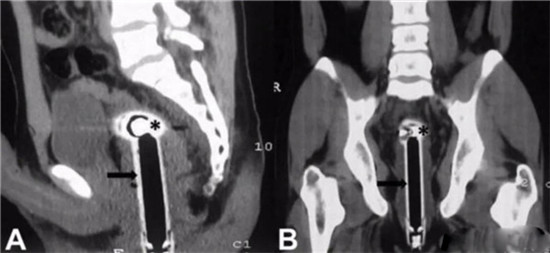

透视下从肛门里夹取直肠里的东西

一般情况下,这些肛门异物的病人,来到医院后,医生都会给他上麻醉。把病人麻醉后,在透视下从肛门里夹取直肠里的东西。

一般情况下,用产钳可以取出大部分直肠异物。